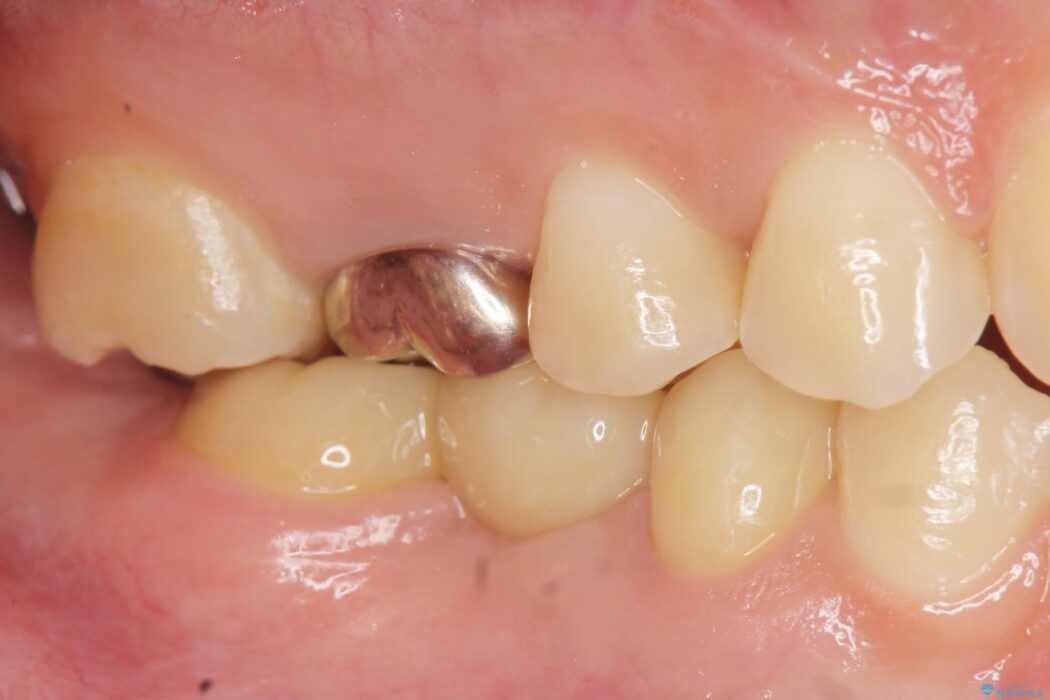

治療後について

欠損した部分が補綴され、普通に噛めるようになったと喜んでいただけました。

本症例では、健康な歯を可及的に守るため神経の処置を避けた上で部分矯正を併用して行うことにより、安全に補綴治療(ブリッジ)ができました。